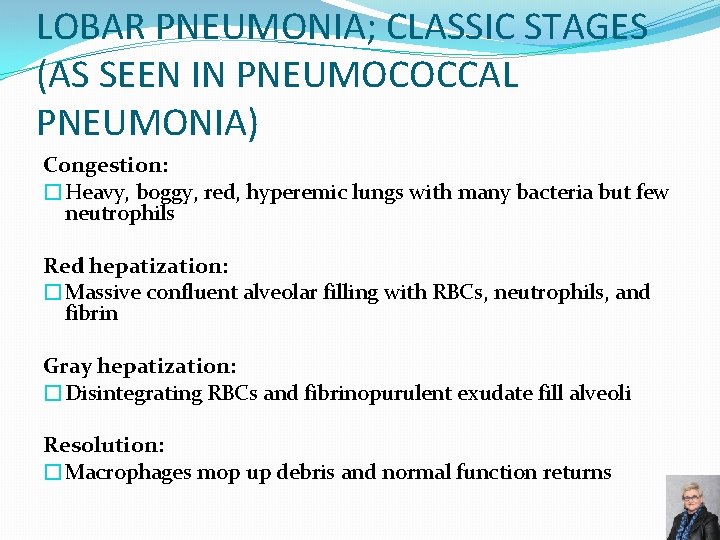

LOBAR PNEUMONIA; CLASSIC STAGES (AS SEEN IN PNEUMOCOCCAL PNEUMONIA) Congestion: �Heavy, boggy, red, hyperemic lungs with many bacteria but few neutrophils Red hepatization: �Massive confluent alveolar filling with RBCs, neutrophils, and fibrin Gray hepatization: �Disintegrating RBCs and fibrinopurulent exudate fill alveoli Resolution: �Macrophages mop up debris and normal function returns 59